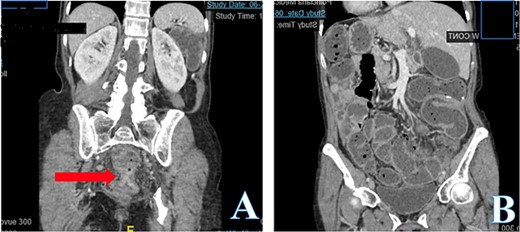

Computed tomography (CT) abdomen and pelvis revealed large bowel obstruction and high-grade stricture, with a miniscule residual lumen (Fig. 1). A nasogastric tube was placed for decompression, with significant output. CT chest showed no evidence of widespread disease. Gastrografin enema was performed to evaluate the obstructive lesion, and to rule out any synchronous proximal lesions, as shown in Fig. 2, no contrast passed beyond the rectal stricture.

Abdomen and pelvis CT scan, coronal view (A) demonstrates low rectal concentric and symmetric near obstructing stricture indicated with the arrow. Coronal view (B) demonstrates a diffuse colonic and small bowel dilation consistent with LBO.